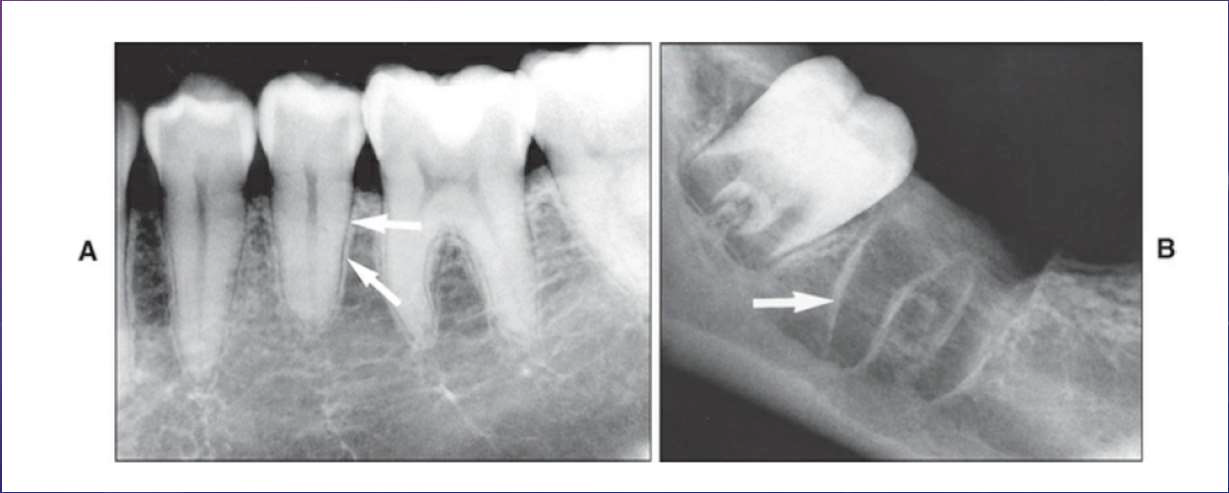

Pulp stone

True (Denticle): 有Dental tubules,跟 Dentin 分離

False (Concentric): 無Dental tubules

Diffuse Pulp Calcification

根管越來越小